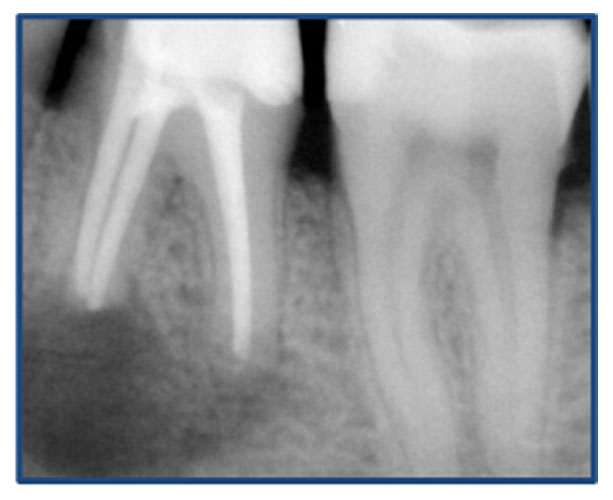

Αρχική εικόνα δοντιού

Εικόνα δοντιού μετά από επανάληψη θεραπείας

Η επανάληψη μιας αποτυχημένης ενδοδοντικής θεραπείας θεωρείται ως η πιο περίπλοκη διαδικασία, που ενέχει αρκετούς κινδύνους για τη μελλοντική λειτουργικότητα του δοντιού. Η απόφαση για επανάληψη είναι συλλογική, μεταξύ της οδοντιάτρου και του ασθενούς, αφού συνεκτιμηθούν μια σειρά παραγόντων με κυριότερους τη διάγνωση της αιτίας της αποτυχίας της προηγούμενης θεραπείας και το όφελος της επανάληψης.

Η επανάληψη μιας ενδοδοντικής θεραπείας δεν σημαίνει και τη διάσωση τελικά του δοντιού. Η δυναμικότητα των παθογόνων αναερόβιων μικροβίων που έχουν αναπτυχθεί στο σύστημα των ριζικών σωλήνων με την συνεπακόλουθη καταστροφή των περιακρορριζικών ιστών καθιστά πολλές φορές αδύνατη τη διατήρηση του δοντιού, ακόμη και με τον συνδυασμό της μικροχειρουργικής ενδοδοντίας.